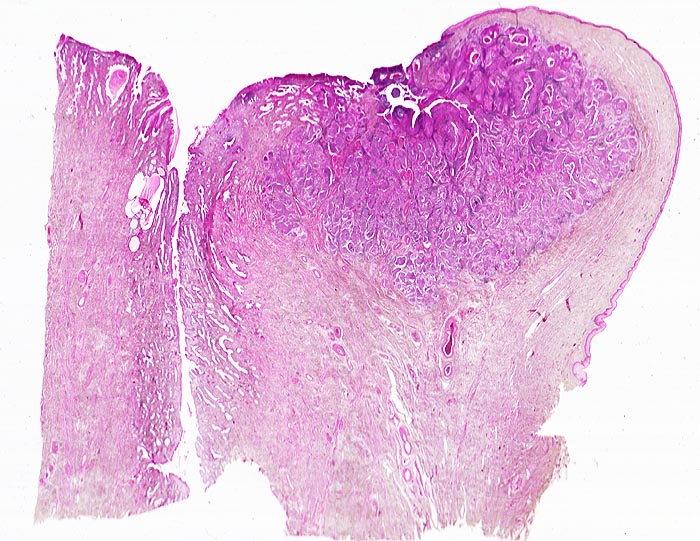

Invasives Plattenepithelkarzinom der Zervix

Scharf begrenzter, von der vorderen Muttermundslippe im Bereich der Umwandlungszone ausgehender Tumor. Zervikalkanal.

Die Umwandlungszone liegt dort, wo das metaplastische Plattenepithel der Ektozervix die endozervikalen Drüsen überwächst. An dieser Stelle finden sich am häufisten präneoplastische und neoplastische Veränderungen des Zervixepithels.